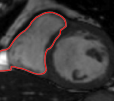

![]() |

| image + boundary | global optical flow | our method | our method (motion decomp.) |